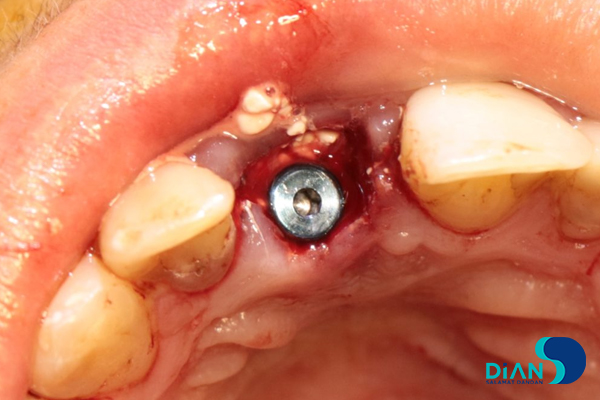

Bio3 implant Progressive 3.8/13 was entered from the box and fixed with 20-25 N/cm2 loading.

Cover screw was placed.

The gap between the implant and the tooth root was filled with bone material.

The screw cap was replaced by the healing abutment.